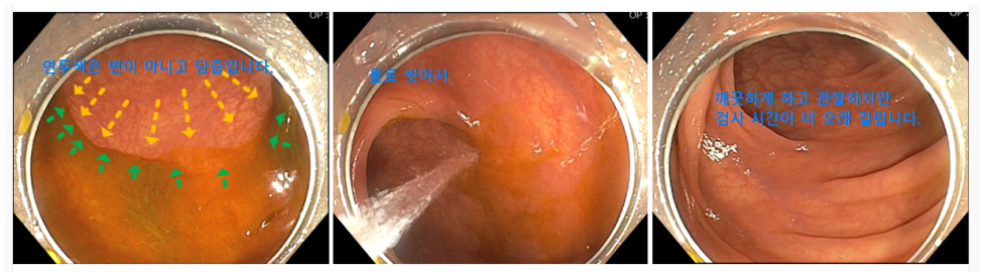

마지막 물 복용은 검사 2시간 전까지 완료해야 합니다. 또한 당일 검사 5-6시간 전에 너무 일찍 약을 마시면 아래 사진처럼 정결이 된 대장 점막에 담즙이 도포되어 씻어서 관찰해야 하므로 검사 시간이 오래 걸립니다.